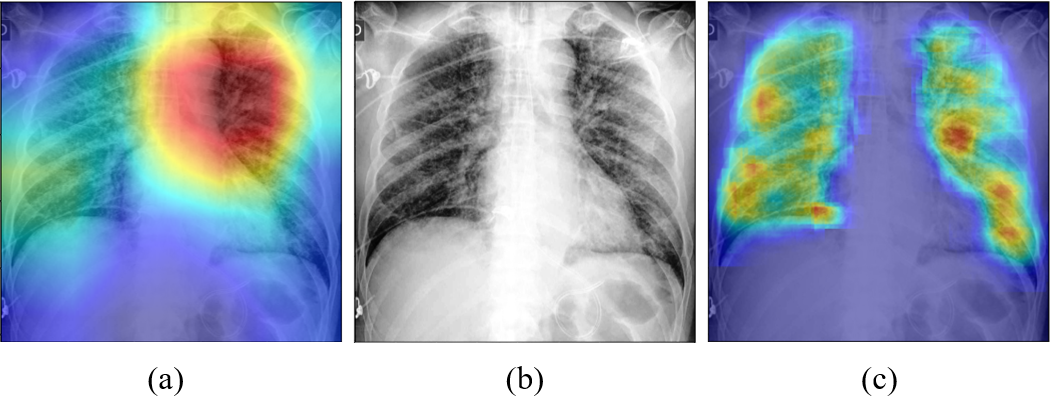

Fig. 7 and Fig. 8 illustrate the examples of visualization of saliency map. As shown in Fig. 7(a), the existing Grad-CAM method for global approach showed the limitation that it only focuses on the broad main lesion so that it cannot properly differentiate multifocal lesions within the image. On the other hand, with the probabilistic Grad-CAM, multifocal GGOs and consolidations were visualized effectively by our local patch-based approach as shown in Fig. 7(c), which was in consistent with the findings reported by clinical experts. In particular, when we compute the probabilistic Grad-CAM for the COVID-19 class using patient images from various classes (i.e., normal, bacterial, TB, and COVID-19), a noticeable activation map was observed only in the COVID-19 patient data set, whereas almost no activations were observed in patients with other diseases and conditions as shown in Fig. 8. These results strongly support our claim that the probabilistic Grad-CAM saliency map from our local patch-based approach is more intuitive and interpretable compared to the existing methods.